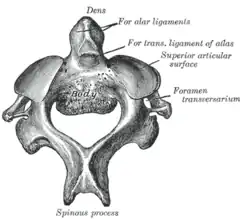

Der Axis unterscheidet sich durch seine Form von allen anderen Wirbeln. Der Wirbelkörper ist relativ groß und massiv. Hervorstechendes Merkmal ist der Dorn oder Zahn des Axis (Dens axis) auf der Oberseite vorne (Mensch) beziehungsweise Vorderseite (vierfüßige Säugetiere) des Wirbelkörpers. Er stellt ontogenetisch den Wirbelkörper des Atlas dar und liegt genau dort, wo diesem fast ringförmigen Wirbel der Körper fehlt. Der Dens geht von der Oberseite des Wirbelkörpers gerade nach oben, besitzt auf seiner Vorder- und Rückseite eine Gelenkfläche und endet mit einer abgerundeten Spitze.[1]

Auf beiden Seiten des Axis geht je ein kurzer Querfortsatz (Processus transversus) ab, der halswirbeltypisch eine runde Öffnung (Foramen transversarium) für die Wirbelarterie umschließt. Rückenseitig schließt sich der ebenfalls recht massive Wirbelbogen an, dessen Ende den kurzen, gegabelten Dornfortsatz (Processus spinosus) trägt. Auf der Ober- und Unterseite liegen je zwei Gelenkfortsätze (Processus articularis superior beziehungsweise inferior) für die Verbindung mit den beiden angrenzenden Wirbeln.[1]